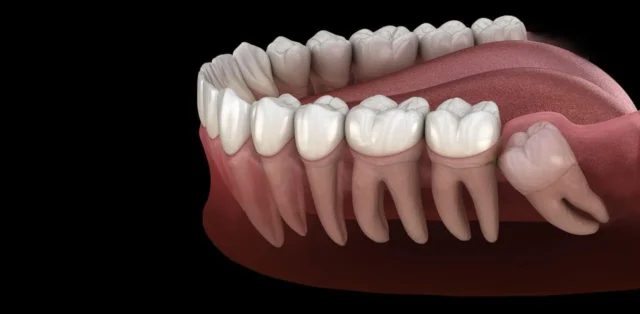

- Răng Khôn (Răng số 8): Là răng mọc cuối cùng (thường từ 17 – 25 tuổi). Đây là răng dễ bị mọc ngầm nhất, chiếm tỷ lệ rất cao. Do không còn đủ chỗ trên cung hàm, răng khôn thường mọc lệch, ngầm hoàn toàn hoặc một phần, gây đau và biến chứng nặng.